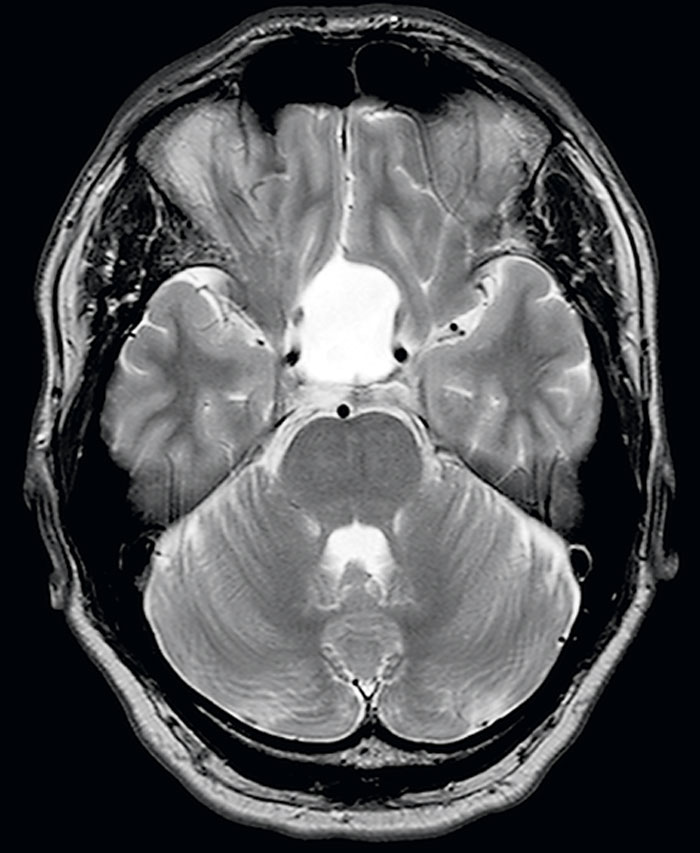

Fallrapport 1 [56] (Fakta 1) rör en 41-årig man som sökte med svår huvudvärk sedan cirka tre månader. Huvudvärken kom i attacker och satt bakom högra ögat/tinningen. Klinisk undersökning/laboratorieprov var u a. Patienten uppfyllde kriterierna för klusterhuvudvärk, och terapi med prednisolon, verapamil, subkutant sumatriptan och 100 procent syrgas (7 l/minut) sattes in. Han svarade på terapin med minskning av huvudvärken efter 15 minuter (syrgas/suma­triptan), och attackerna minskade betydligt i frekvens. Då attackerna fortsatte sökte han igen efter tre veckor. Förnyad klinisk undersökning var normal. MR hjärna med kontrast visade en expansiv högersidig parietal tumör med ödem, förenlig med gliom (Figur 1). Resektion av tumören utfördes, och PAD visade glioblastoma multiforme. Huvudvärken försvann helt efter operationen. Han var huvudvärksfri vid uppföljning efter tolv månader trots utsättning av tidigare läkemedel.

Figur 1. MR hjärna med kontrast, T1-viktade bilder, visar ett parietalt glioblastoma multiforme med expansiv effekt i höger hemisfär.